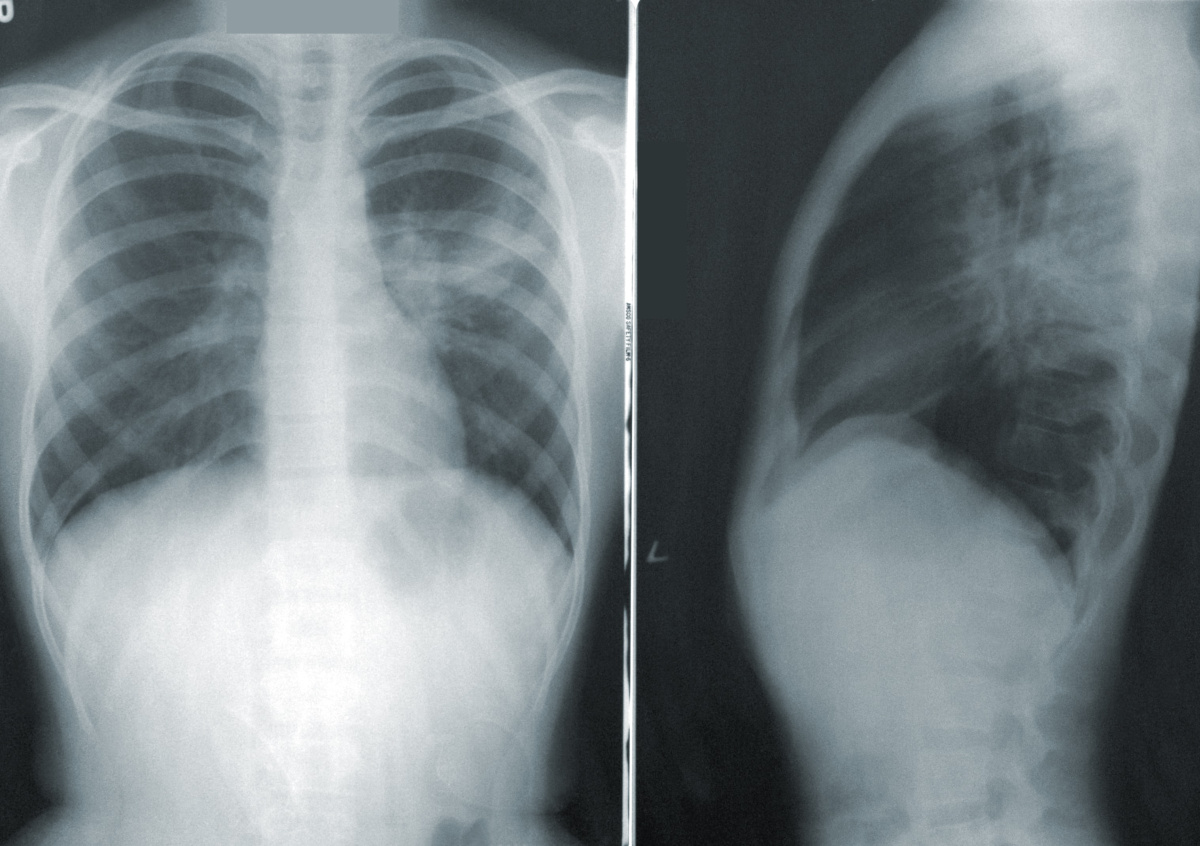

Фото: Unsplash